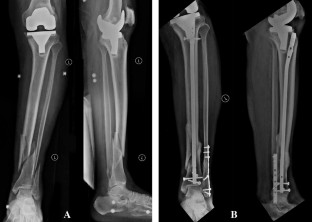

Between 2017 and 2018, three patients with acute tibial shaft fractures distal to a TKA (Felix Type 3A) were treated with an intramedullary nail. Preoperative planning involved assessing proximal tibia to ensure adequate room for implant and instrumentation. The average patient age was 66.3 years (range 59–72 years) and all patients were males. All the patients sustained fractures of distal tibial and fibula diaphysis, after a road traffic accident. There were no complications intraoperatively, and all procedures were completed uneventfully. One patient underwent additional fixation of the fibula.

All patients achieved a radiological fracture union after an average of 20.6 weeks. There were no fixation failures, or nonunions postoperatively. There were no new symptoms relative to the TKA that could be attributed to the tibial nailing procedure.

Fig. 1